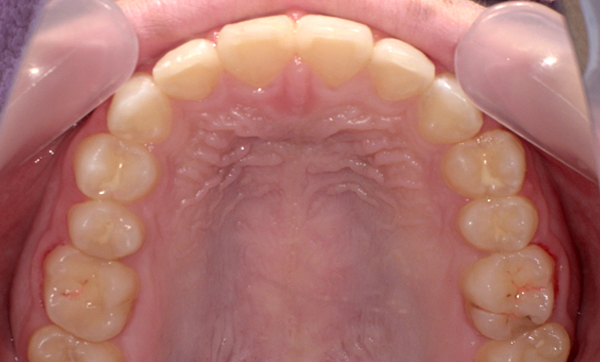

| 治療前 | 治療後 |

|---|---|

|